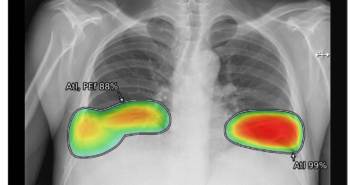

의료 인공지능(AI) 기업 루닛이 국립경찰병원(이하 경찰병원)과 흉부 엑스레이 AI 영상분석 솔루션 ‘루닛 인사이트 CXR’의 공급 계약을 체결했다. 루닛 인사이트 CXR은 AI 기반 기술을 활용해 폐 결절, 폐 경화, 기흉 등 10가지 흉부 질환을 판독해 의료진을 보조하는 소프트웨어다. 이번 계약에 따라 루닛은 향후 1년간 경찰병원에 루닛 인사이트 CXR을 공급해 경찰 및 소방 공무원을 비롯한 내원 환자들의 폐 질환 진단을 돕는다. 구체적으로 경찰병원은 응급실 및 호흡기내과 등 환자 검진 과정에서 루닛의 AI 솔루션을 활용해 흉부 엑스레이 영상을 정밀 판독할 예정이다. 김진학 경찰병원 병원장은 “루닛 인사이트 CXR은 우리 병원의 흉부영상판독에 유용하다고 판단하여 사용하게 됐다. CXR 도입으로 판독 시간 단축과 진단정확도 향상을 통해 환자에게 보다 나은 의료 서비스 제공을 기대한다”고 말했다. 한편 루닛은 지난 2019년 보건소를 시작으로 국군수도병원 및 연평부대 등 군 병원과 지방의료원에 매년 의료AI 솔루션을 신규 도입한 데 이어 올해 해외 군 병원과 경찰병원에까지 제품을 공급하며 공공의료 사업분야를 지속 확대해 나가고 있다. 관련 기사 더보기 https://www.venturesquare.net/887160